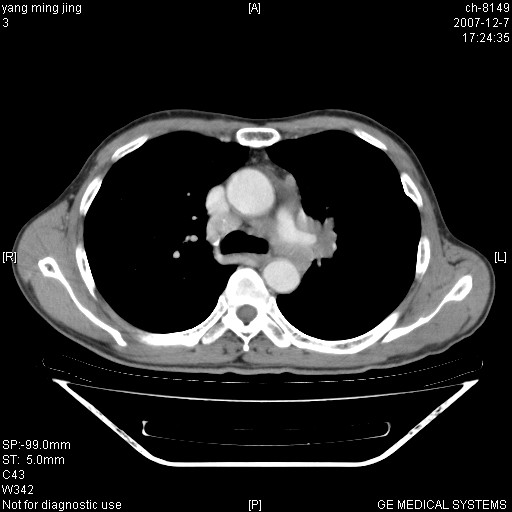

以下是引用zsl6918在2007-12-7 22:22:00的发言:[br]左肺上叶中心性肺癌并肺内及纵隔淋巴结转移,肝内转移。小细胞肺癌可能性大。

以下是引用狙击手在2007-12-8 11:03:00的发言:[br]考虑:左肺上叶中心性肺癌并肺内及纵隔淋巴结转移,肝内转移。